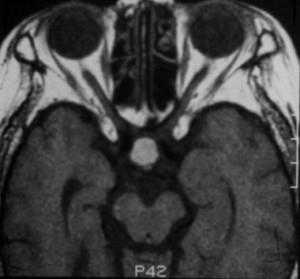

Киста кармана Ратке представляет собой редко встречающееся образование из остатков эмбриональной эктодермы (щель Ратке), расположенное между долями гипофиза. Выявляется в любом возрасте, но чаще в 50-60 лет. Клинические проявления связаны с масс-эффектом. При МРТ головного мозга выявляется небольшая (3-5мм) киста с четким контуром, без отека вокруг, однородная по структуре. Сигнал на МРТ головного мозга зависит от содержимого. При серозном содержимом сигнал типично жидкостный, при мукоидном киста светлая на Т1-взвешенных МРТ головного мозга. В 70-80% случаев внутри кисты выявляется неконирастирующийся узелок («пятно») - признак патогномоничный для кисты кармана Ратке. В редких случаях киста достигает больших размеров и даже выходит за пределы седла. Стенка кисты иногда усиливается при МРТ головного мозга с контрастированием. Дифференциальная диагностика при МРТ головного мозга должна проводиться с арахноидадьной и эпидермоидной кистами, тератомой, кистозной аденомой гипофиза и краниофарингиомой. Иногда при МРТ головного мозга киста кармана Ратке напоминает “пустое” турецкое седло. При маленьких размерах кисты ее на до дифференцировать на МРТ с микроаденомой гипофиза.

![Ratke cleft cyst]()

МРТ головного мозга. Т1-взвешенная сагиттальная МРТ. Киста кармана Ратке.